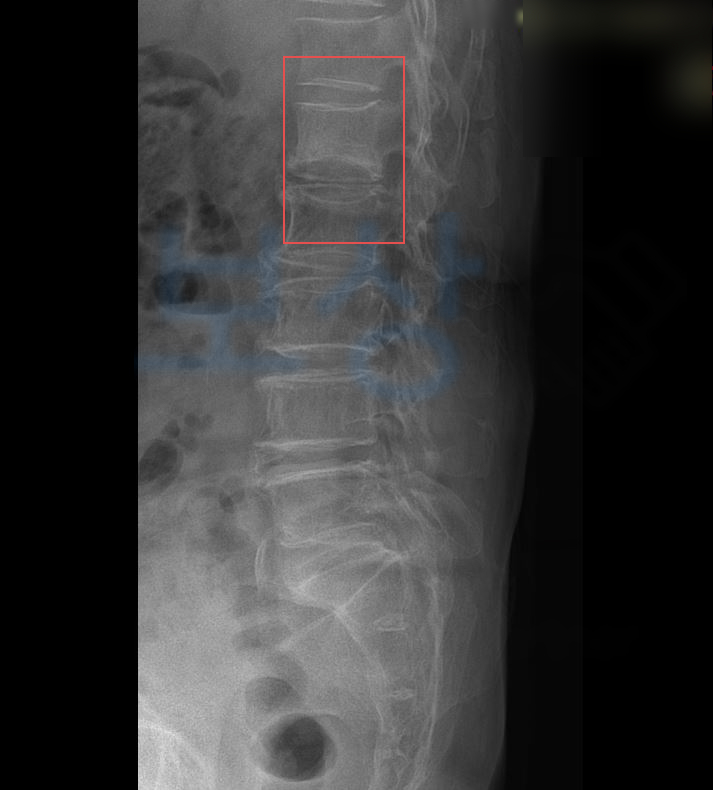

위 사고로 이@@님은 극심한 허리 통증을 호소했고 정밀 검사 상 나온 진단명은

L1 부위의 골절 s32020

경추 염좌, 요추 염좌 진단을 받으셨습니다.

**척추에 경미한 장해 15%**에 해당하셨습니다. 저희는 위 진단서를 기초로 손해사정서 및 관련 증빙서류를 검토 및 준비하여 보험사에 청구하였습니다. 물론 보험사에서는 심사를 진행하여 내부자문, 의료자문등을 거쳐 약 2달간의 분쟁이 오갔지만, 결국!